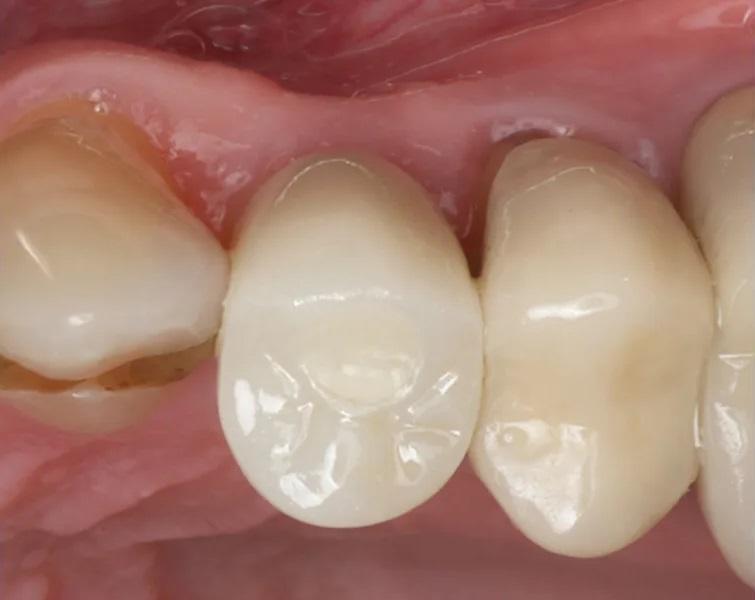

Пациент мужского пола 68 лет был направлен эндодонтистом с диагнозом симптоматический необратимый пульпит с нормальными периапикальными тканями и значительной потерей костной ткани с вовлечением фуркации у первого премоляра верхней челюсти слева (зуб № 2.4). Из-за состояния пародонта была показана реабилитация с помощью имплантационной реставрации. Конусно-лучевая компьютерная томография (КЛКТ) выявила потерю кости с дистальной стороны пораженного зуба, размером 5 мм в ширину и 9 мм в длину соответственно, с вовлечением альвеолярного костного гребня (Фото 1 – Фото 4).

Фото 1. Предоперационный интраоральный передний вид.

Фото 2. Предоперационный интраоральный латеральный вестибулярный вид.